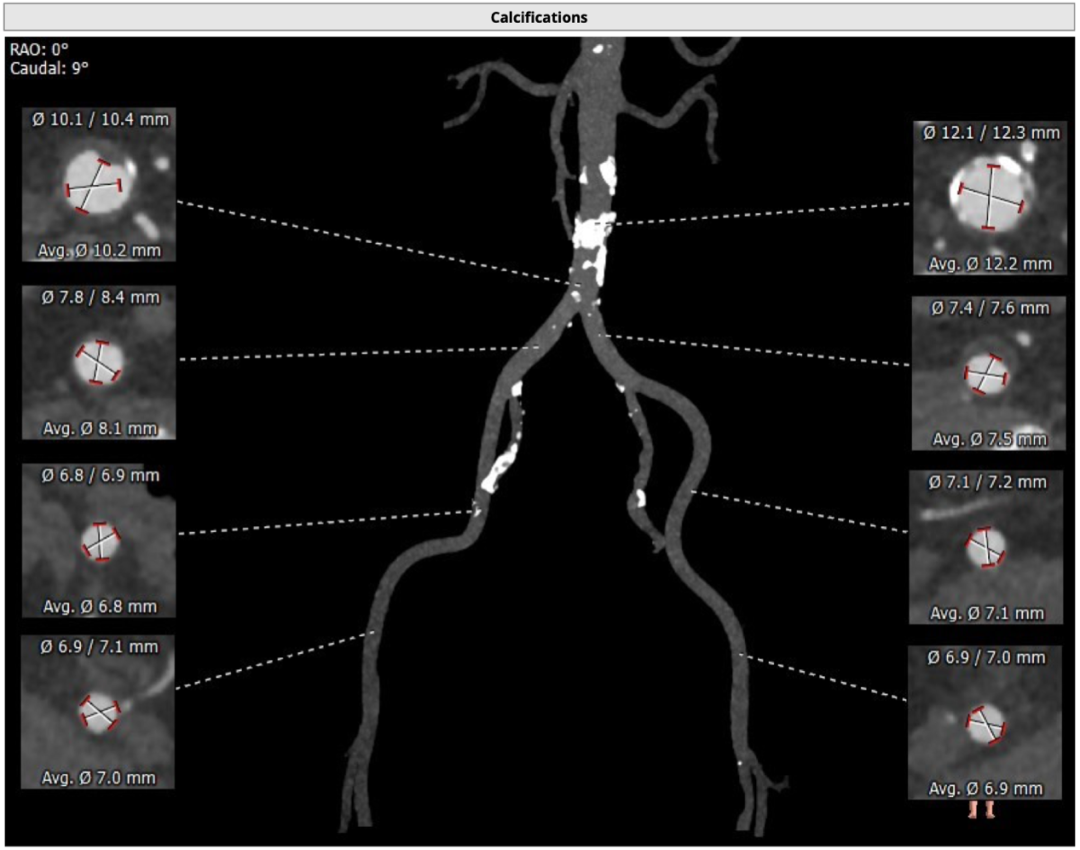

主动脉根部评估

CT 数据显示该患者为Type1型二叶式主动脉瓣

主动脉瓣瓣环周长72.5mm,周长径23.1mm

LVOT 周长 85.1mm,周长径27.1mm

SOV:31.1mm*33.6mm*31.6mm

STJ 周长 91.9mm

无冠瓣钙化严重,HU850:448mm³

瓣环水平夹角46度

血管外周入路评估